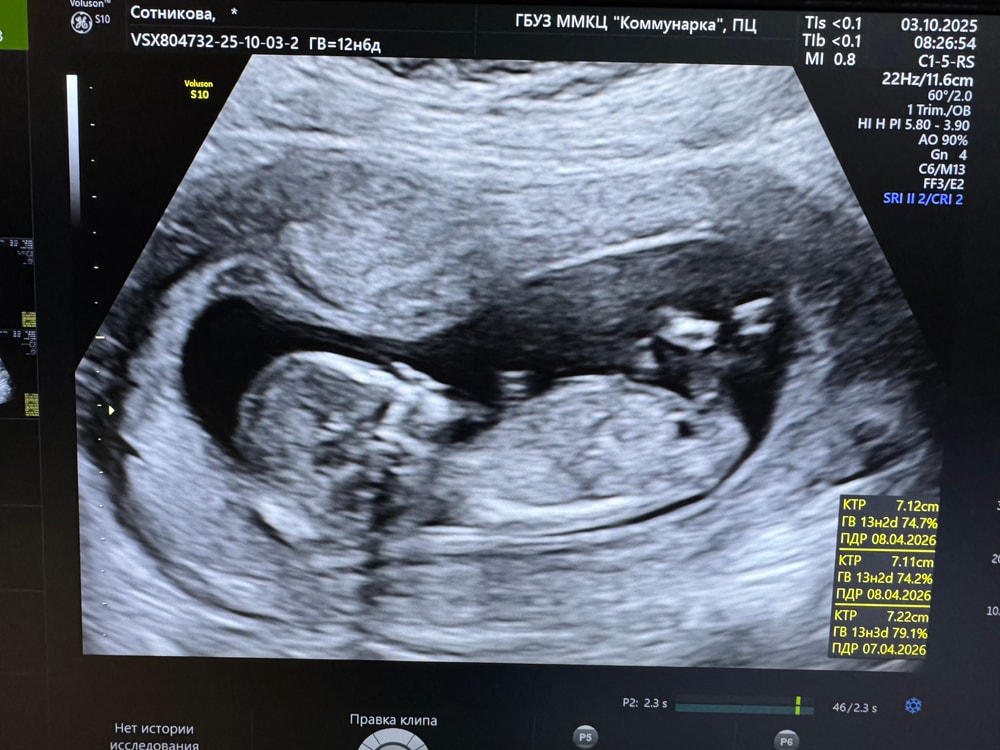

1 скрининг ❤️

УЗИ, КТГ, доплерСходили мы сегодня с мужем на скрининг ) Ожидали одно, реальность другое 😁

Давайте гадать по фото))) тааак интересно, кто там ☀️

ЧСС - 165